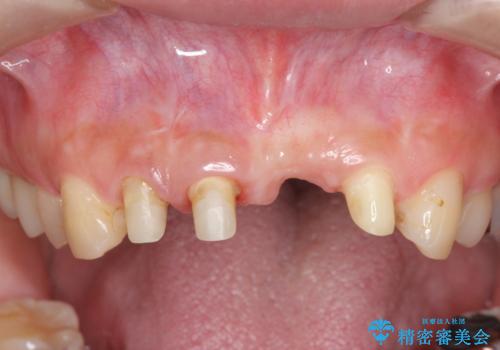

左側の前歯には他院で埋入されたポジションの悪いインプラント補綴により歯冠長の長いクラウンが装着されており、感染による排膿も認められこのまま審美性を改善するのは難しい状態です。

不良インプラントを除去し最終的にブリッジによる補綴で審美性の改善を行うこと、その準備として骨の造成・歯肉の移植による歯の欠損部顎堤のボリュームを維持・増大を計画します。

感染したインプラントからは排膿が間欠的に認められ、掻爬・除去が検討されうるような状況でした。

より審美的な改善を強く求められたため、インプラントを除去し可及的に欠損部顎堤を増大したのちブリッジによる審美改善を行いました。